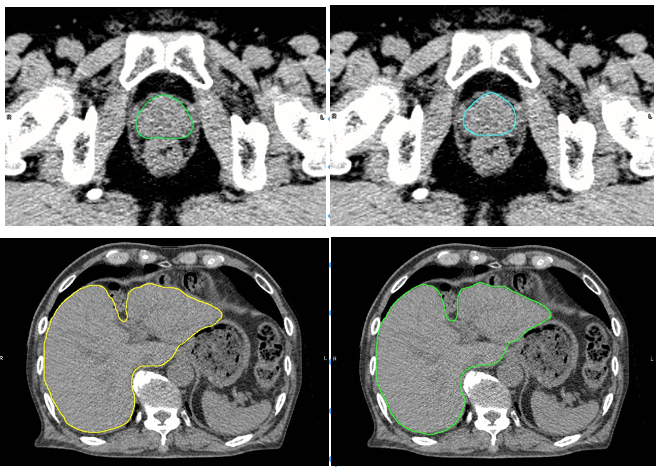

肝臓モデルを使用した例では、輪郭作成に要する時間は、従来の手作業のみでは30分以上要したものが、臨床利用ための人による修正時間も含め、Ai-Segによる自動輪郭作成及び必要に応じての軽微な修正作業を合わせて5分程度までに短縮することができました。図1に示すように医師とAi-Segが作成した輪郭を比較しても違いがわからないほどの水準にまで達しています。

図の上は前立腺、下は肝臓のCT画像。左はAi-Segによる自動抽出、右は医療従事者の手入力による抽出。Ai-Segによる描画は医療従事者による描画と遜色ない精度で輪郭を自動作成が可能(図の提供:大阪大学プレスリリースより※)